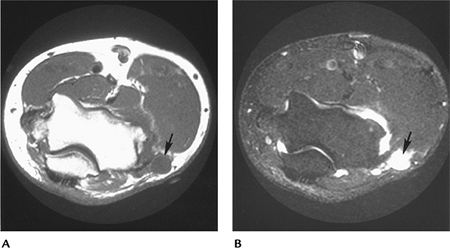

![]() |

FIGURE 8-28 Ganglion cyst. Axial T1- (A) and T2- (B) weighted images showing a benign cyst (arrow) with uniform increased intensity on T2-weighted and low signal intensity on T1-weighted sequences.

P.551

FIGURE 8-29 Malignant fibrous histiocytoma. Axial T1- (A) and T2-weighted (B) images of this malignant lesion. Signal inhomogeneity is most easily appreciated on the T2-weighted image (B).

Neoplasms: Soft Tissue Tumors

Key Facts

Soft tissue tumors are most effectively identified and categorized with MRI.

As a general rule, benign lesions are well defined, with homogeneous signal intensity.

Malignant tumors are inhomogeneous,

Intravenous gadolinium is useful to